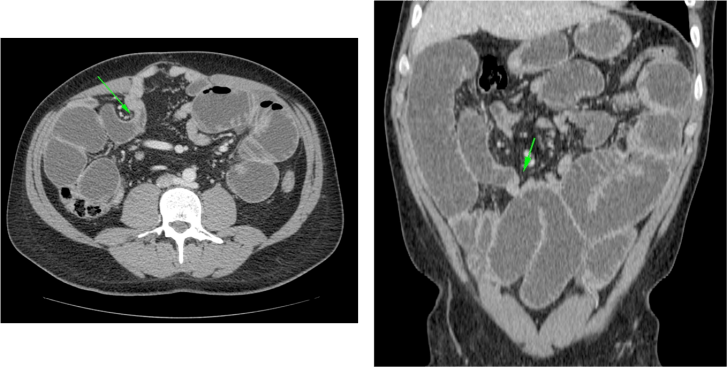

INVAGINACIÓN INTESTINAL.

La invaginación intestinal es la introducción telescópica de un segmento de intestino junto con su mesenterio, dentro de la luz de otro segmento contigüo más distal. En una invaginación, la porción de intestino que se invagina, arrastra su meso acompañante, lo cual origina una compresión del retorno venoso. Si esto no se soluciona a tiempo, se produce edema, hemorragia, obstrucción y gangrena.

El diagnóstico actual de la se realiza mediante TC abdominal:

- El hallazgo patognomónico es el signo de la escarapela o diana identificable en la TC o ecografía.

- Podemos ver la imagen de “Intestino dentro de intestino” gracias a las reconstrucciones multiplanares.

Invaginación de Intestino Delgado

- Son más frecuentes que las de colon

- Es más frecuente la invaginación esporádica. Si hay lesión subyacente, suele ser benigna.

- Las causas malignas son menos frecuentes (15-30%), en general metástasis, sobre todo de melanoma.

- El linfoma constituye el 20-40% de todos los tumores malignos de ID.